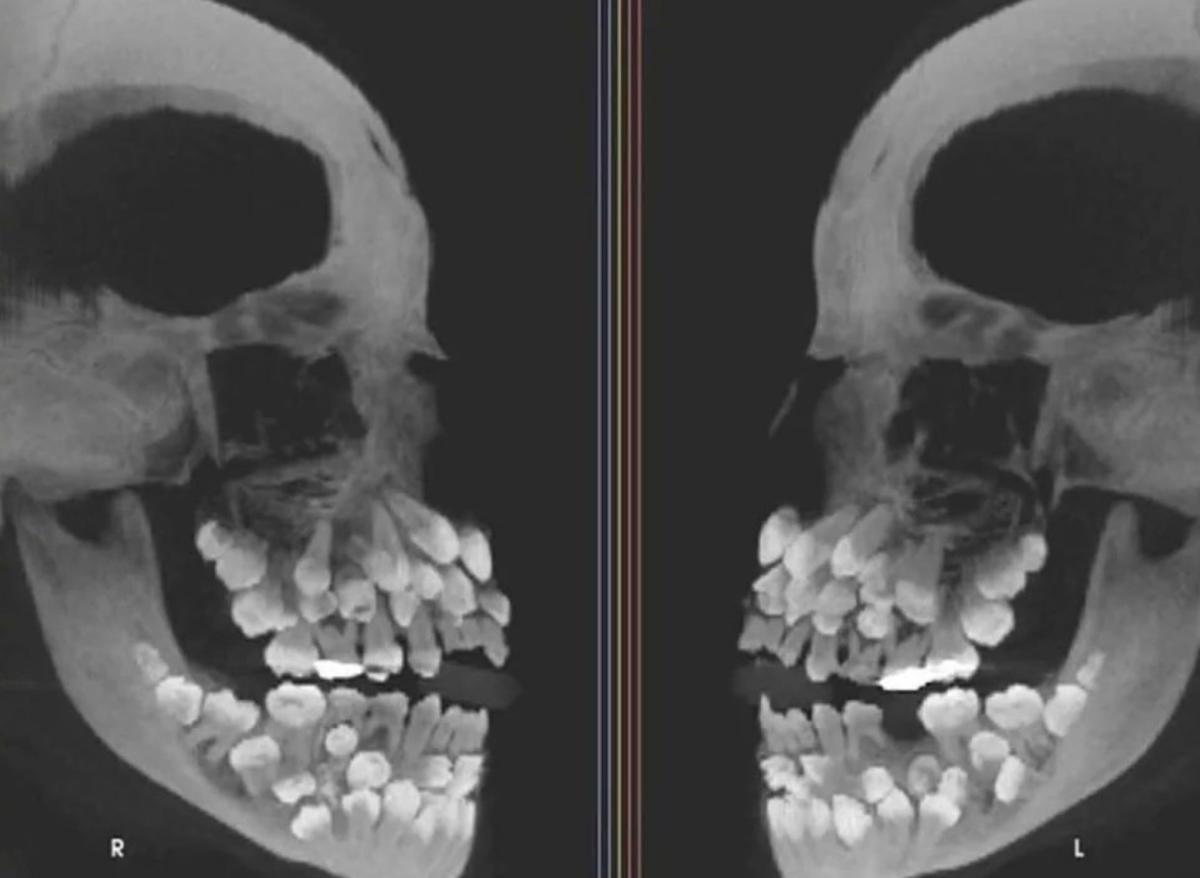

브라질의 11세 소녀가 유치를 뽑으러 갔다가 입안에 수십 개의 치아가 숨어있다는 사실을 알아냈다.

소녀의 치아는 총 81개로 세계적으로 드문 사례다.

■ “다발성 과잉치증”…30개 넘는 과잉치는 극히 이례적

그런데 이 소녀는 유치 18개에 영구치 32개, 과잉치가 31개였다.

소녀를 진료한 병원 연구진은 “이런 상태는 ‘다발성 과잉치증’”이라며 “과잉치는 보통 한두 개 생기는데, 30개가 넘는 경우는 거의 없다”고 설명했다.

과잉치는 정상보다 많은 치아가 자라는 현상으로, 보통 잇몸 속에 숨어 있거나 다른 치아와 겹쳐 나와 치열을 무너뜨릴 수 있다. 심한 경우 턱관절 통증이나 인접 치아 손상까지 이어질 수 있다.